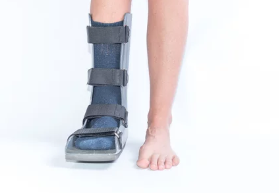

- 복합 골절: 뼈가 여러 조각으로 나뉘거나, 관절에 영향을 미치는 경우에는 6주에서 8주 이상이 걸릴 수 있습니다. 이 경우 물리치료와 보조기구 사용이 필요할 수 있습니다.

발가락 골절은 심각한 경우 수술이 필요할 수 있지만, 대다수의 경우 비수술적 치료로 관리할 수 있습니다. 골절 치료의 목적은 뼈를 고정하고 자연스럽게 붙을 수 있도록 돕는 것입니다.

- 휴식: 발가락 골절의 회복 과정에서 휴식은 매우 중요합니다. 체중 부하를 최소화하고, 목발을 사용하여 발가락에 압력을 줄이지 않도록 해야 합니다.

- 목발 사용: 골절 초기에는 발가락에 체중이 실리지 않도록 목발을 사용하는 것이 좋습니다.

- 신발 선택: 회복 중에는 단단한 밑창이 있는 신발을 신어 발가락을 보호하고, 충격 흡수가 되는 신발을 착용하는 것이 좋습니다.